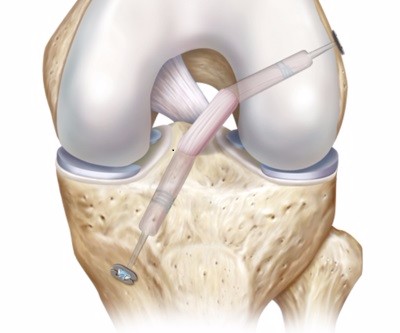

Anterior Cruciate Ligament Reconstruction Rehabilitation

A guide for you rehabilitation after ACL reconstruction that you can work through with your physiotherapist.

Download Protocol Document.svg)